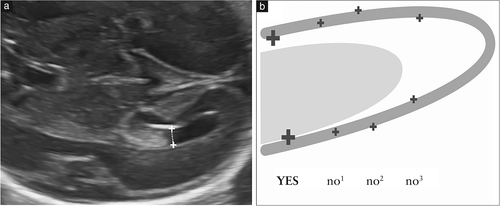

建议进行脑室测量,因为多项研究表明,这是评估脑室系统完整性的最有效方法,而脑室扩张是大脑异常发育的常见标志。在垂直于侧脑室的的脉络丛神经球水平进行测量,将卡尺放置在侧壁产生的回声内(图5)该测量值在妊娠中期和晚期保持稳定,平均直径在6至8mm18之间; <10mm认为是正常的。尽管此临界值是在几年前确定的,但即使使用更现代化的设备,尤其是在妊娠期,它仍然有效。因此,应将侧脑室宽度≥10mm视为可疑。在这里需要强调的是:(1)妊娠期间侧脑室宽度可能会发生变化,增加或减少;(2)如果两个侧脑室的尺寸均小于10mm,则两侧之间的侧脑室宽度中度不对称应视为正常。

图5(a)侧脑室房宽度的测量。卡尺位于脉络丛球的水平,位于侧脑室壁产生的回声内。(b)图示了正确的卡尺位置,以进行侧脑室测量。当卡住侧脑室壁的最宽部分的内边缘并垂直侧脑室的长轴对齐时,卡尺放置正确(是)。不正确的放置位置包括中-中(no1),外-外部(no2)以及在侧脑室较窄的部分中过于靠后或不垂直于心室轴的位置(no3)。